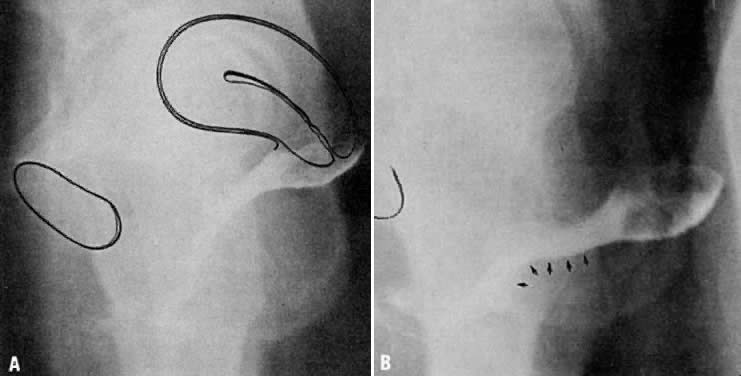

The vagina in the cadaver is usually depicted as an almost straight hollow tube extending vertically upward toward the sacral promontory. In the living healthy female, however, the upper vaginal axis lies in an almost horizontal plane when the patient is in a standing position. Radiographic colpography has demonstrated a distinct, superiorly convex, perineal curve in the lower vagina (Fig. 1).5 The upper vagina lies on the rectum, which, in turn, lies on and parallel to the levator plate. It is this almost horizontal position of the supporting levator plate that accounts for a similar axis to the vagina. The levator plate is formed by the fusion of the levator ani muscles posterior to the rectum, from just behind the levator hiatus to their coccygeal insertion (Fig. 2). The rectum, vagina, and urethra pass through the levator hiatus, and if the levator ani muscle is defective, the inclination of the plate will be downward and the hiatus will sag. Although the cervix and upper vagina have considerable mobility, they are more or less anchored in position over the levator plate by the cardinal ligaments. The length and flexibility of these ligaments normally permit the cervix and upper vagina to be moved in any direction over the rectum on the levator plate but not anterior to the margin of the genital hiatus.

Fig. 1. A and B. Normal vaginal depth and axis. Colpogram of healthy 25-year-old nulligravida. The vaginal walls are painted with barium paste. The patient is standing at rest (A). The position of the symphysis is outlined to the left. The effect of straining by a Valsalva maneuver is shown (B). The perineal curve of the lower vagina is unchanged, but the horizontal axis of the upper vagina is accentuated with straining.(Nichols DH, Milley PS, Randall CL: Significance of restoration of normal vaginal depth and axis. Obstet Gynecol 36:251, 1970)